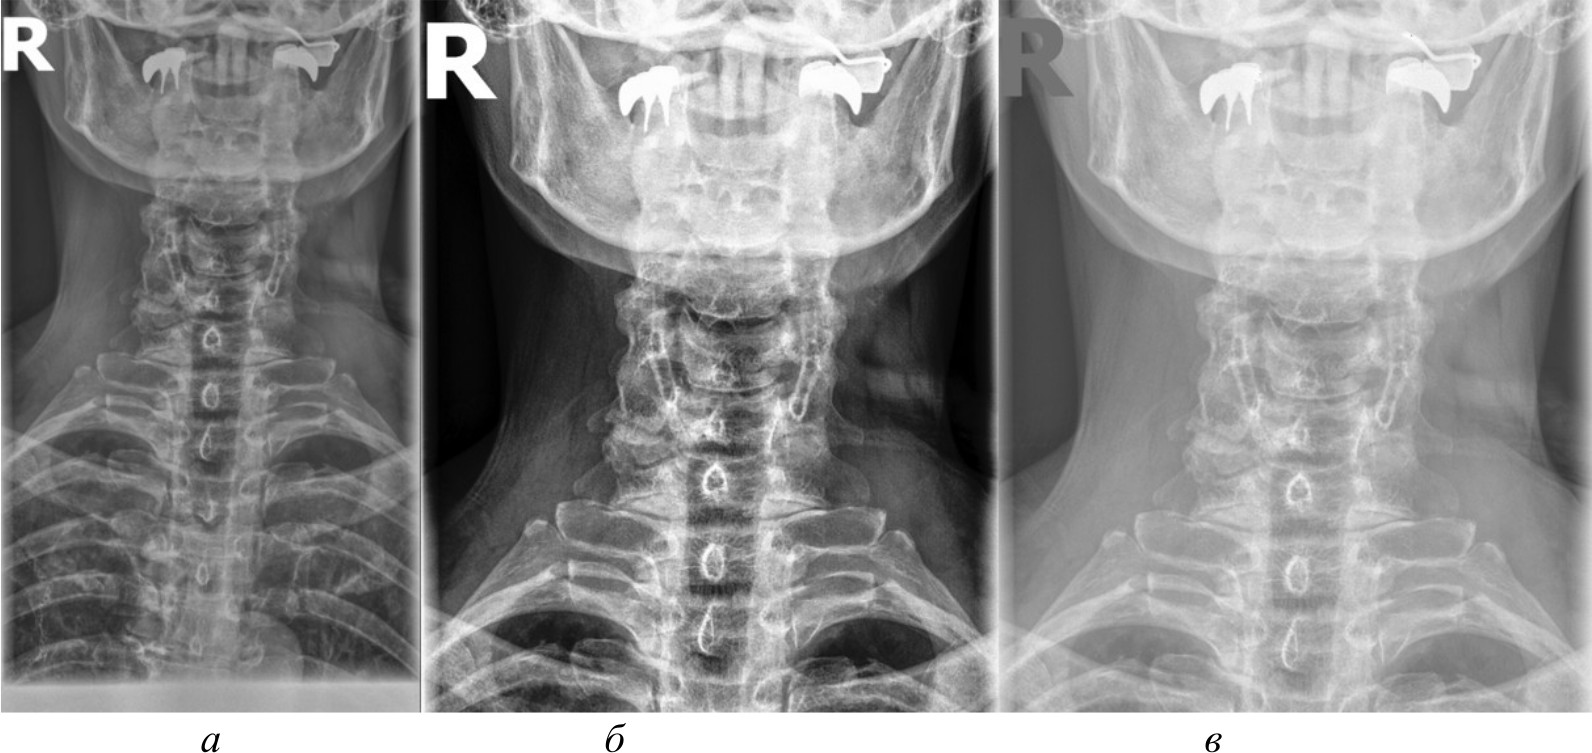

Для создания эталонного набора изображений рентгеновские снимки в формате DICOM были загружены в специализированное программное обеспечение для медицинской визуализации. DICOM является стандартным форматом для медицинских изображений, который позволяет сохранять изображение с высоким качеством и дополнительной информацией об исследовании. Однако для дальнейшей обработки и анализа эти DICOM-файлы конвертируются в более распространенные графические форматы. Специализированное программное обеспечение сохраняет их в формате PNG. На рис. 2, а представлено изображение, полученное в результате работы в специализированном программном обеспечении.

Несмотря на то, что PNG является одним из четких графических форматов, он все же может приводить к некоторой потере качества по сравнению с исходными DICOM-файлами. Поэтому для извлечения более качественных изображений и проведения более детального анализа применяются алгоритмы и методы компьютерного зрения, которые способны работать непосредственно с DICOM-данными, избегая потерь при конвертации.

Для сравнительного анализа использовались различные методы и алгоритмы компьютерного зрения. Помимо изображений в формате PNG, конвертированных из исходных DICOM-файлов, применялись и другие подходы, направленные на извлечение более качественных изображений непосредственно из DICOM-данных, среди которых:

- базовое отображение Python. Изображения загружены в Python и отображены при помощи библиотеки Pillow без применения каких-либо дополнительных преобразований. Данный метод представлен на рис. 2, б;

- медианный фильтр. Для сглаживания шумов и артефактов на изображениях к базовому отображению Python применен медианный фильтр из библиотеки OpenCV. Размер окна фильтра был подобран эмпирически. Данный метод обработки представлен на рис. 2, в;

- адаптивная эквализация гистограммы. Для улучшения локального контраста изображений помимо базового отображения Python использована адаптивная эквализация гистограммы из библиотеки OpenCV. Метод адаптивной эквализации представлен на рис. 3, a;

- стандартная эквализация гистограммы. Для сравнения с адаптивной эквализацией помимо базового отображения Python применена стандартная эквализация гистограммы из OpenCV. Данный метод представлен на рис. 3, б;

- гамма-коррекция. Для регулирования яркости и контрастности изображений, а также для сравнения с двумя предыдущими эквализациями использована гамма-коррекция. Значение гамма-параметра подбиралось эмпирически. Гамма-коррекция представлена на рис. 3, в.

Рис. 2. Изображение, полученное при помощи специализированного программного обеспечения (а), метод базового отображения в Python (б), метод базового отображения Python с применением медианного фильтра (в)